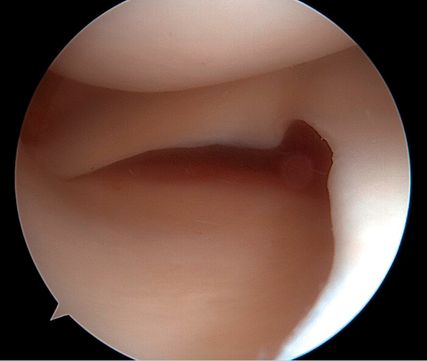

Arthroskopische Instabilitätszeichen: „floating meniscus“ und „drive-through sign“

In einer Level-I-Studie an Patient:innen mit kombinierten VKB- und Grad-II-MCL-Verletzungen (nach Fetto und Marshall) und „Floating-Meniskus-Zeichen“ zeigte die Patientengruppe nach MCL-Augmentation mittels gestielter autologer Gracilis-Sehne signifikant weniger VKB-Revisionen, eine geringere residuale MCL-Laxität sowie bessere patient:innenberichtete Outcome-Scores nach 24 Monaten im Vergleich zu Patient:innen mit isolierter VKB-Rekonstruktion und konservativ behandeltem MCL. Die Abbildung 1 zeigt das „Floating-Meniskus-Zeichen“, ein arthroskopisches Zeichen der medialen Instabilität, bei dem sich der mediale Meniskus vom tibialen Plateau abhebt, infolge einer meniskotibialen Läsion des tiefen Innenbandes. Aufgrund einer zusätzlichen Läsion des oberflächlichen Längsbandes kommt es zu einer medialen Gelenköffnung, die als „medial drive-through sign“ bezeichnet wird.